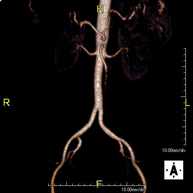

Prueba diagnóstica no invasiva que consiste en el estudio de la arteria aorta abdominal, obteniendo imágenes de alta definición anatómica mediante el empleo de un campo electromagnético y ondas de radio (con un emisor y un receptor). Es indispensable el uso de contraste paramagnético (Gadolinio). Sin embargo, no utiliza radiación ionizante. La calidad de las imágenes permite realizar reconstrucciones en 2D y 3D. Está indicado en aquellos pacientes con enfermedad vascular (aterosclerosis), estudio de aneurismas, en estudios pre-quirúrgicos de lesiones adyacentes a la aorta abdominal como "mapa" vascular, etc. - Angio RM Aorta-ilíaca

Prueba diagnóstica no invasiva que consiste en el estudio de la arteria aorta abdominal de las arterias ilíacas, obteniendo imágenes de alta definición anatómica mediante el empleo de un campo electromagnético y ondas de radio (con un emisor y un receptor). Es indispensable el uso de contraste paramagnético (Gadolinio). Sin embargo, no utiliza radiación ionizante. La calidad de las imágenes permite realizar reconstrucciones en 2D y 3D. Esta prueba está especialmente indicada como estudio pre-quirúrgico (mapa vascular) antes de intervenciones percutáneas o quirúrgicas de aorta abdominal y arterias ilíacas, estudio complementario en pacientes con isquemia de miembros inferiores, etc. - Angio RM Arterial extremidades inferiores